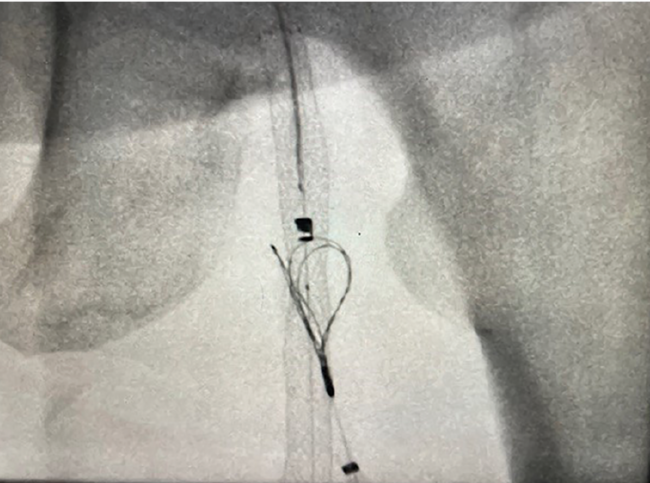

The procedure on her left leg took approximately 120 minutes, and she did exceptionally well (Figures 1A-D). The revascularization was successful and her left leg healed as expected. About a month later, she returned to us and, to our surprise, asked if we could perform the same procedure on her right leg. She was impressed by how much easier the percutaneous bypass was compared to her previous experience with open surgical bypass, which had been a challenging and difficult course for her.

We proceeded with the procedure on her right leg, and once again, the results were excellent. This case serves as a great example of how PTAB with the DETOUR System can effectively treat bilateral SFA disease, even when the severity of disease differs between the legs. One leg was treated for critical limb ischemia, while the contralateral leg was treated for claudication. Her follow-up appointments have shown remarkable results, with the patient very satisfied with her outcome, and she continues to do well.